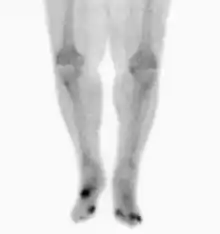

Osteomyelitis in both feet as seen on bone scan

The diagnosis of osteomyelitis is complex and relies on a combination of clinical suspicion and indirect laboratory markers such as a high white blood cell count and fever, although confirmation of clinical and laboratory suspicion with imaging is usually necessary.[20]

Nuclear medicine scans can be a helpful adjunct to MRI in patients who have metallic hardware that limits or prevents effective magnetic resonance. Generally a triple phase technetium 99 based scan will show increased uptake on all three phases. Gallium scans are 100% sensitive for osteomyelitis but not specific, and may be helpful in patients with metallic prostheses. Combined WBC imaging with marrow studies have 90% accuracy in diagnosing osteomyelitis.[22]